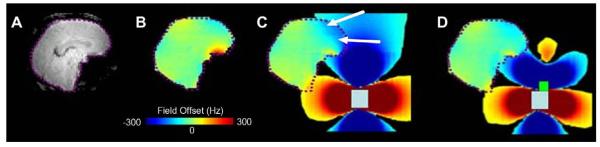

Fig. 1 shows (A) a fast-spin-echo (FSE) anatomic image of an axial slice (6 mm thick) through the frontal cortex of the human brain at B0 = 3T, (B) a ΔB0 field map over the same slice, (C) signal loss in weighted (TE = 35 ms) gradient-echo images (most prominent loss indicated with orange arrow), and (D) distortion in EPI images (indicated with green arrows), collected with TE = 25 ms, 64 × 64 in plane pixels over a 20 cm × 20 cm FOV, a readout bandwidth of 250 kHz. Arrows indicate directions of distortion in the phase-encoded dimension. The effects of B0 inhomogeneity on signal loss and EPI geometric distortion are clear.

Fig. 1.

(A) Fast-spin-echo (FSE) anatomic image of an axial slice (6 mm thick) through the frontal cortex of the human brain at B0 = 3T. (B) ΔB0 field map over the same slice, (C) signal loss in weighted (TE = 35 ms) gradient-echo images (most prominent loss indicated with orange arrow), and (D) distortion in EPI images (indicated with green arrows), collected with TE = 25 ms, 64 × 64 in plane pixels over a 20 cm ×20 cm FOV, a readout bandwidth of 250 kHz. Arrows indicate directions of distortion in the phase-encoded dimension.